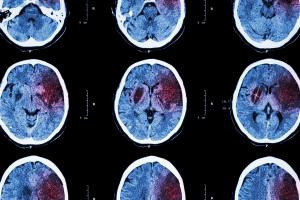

MÉNOPAUSE : Un peu de matière grise en moins ?

La ménopause entraîne aussi une diminution de la matière grise avec, chez certaines femmes des symptômes associés, dont une dégradation de la santé mentale, une augmentation des niveaux d’anxiété et de dépression et des troubles du sommeil. C’est la conclusion de cette équipe de psychologues et de neuroscientifiques de l’Université de Cambridge, qui précise que le traitement hormonal substitutif (THS) ne semble pas atténuer ces effets, bien qu’il puisse ralentir le déclin d’une des fonctions cognitives impactées, le temps de réaction.